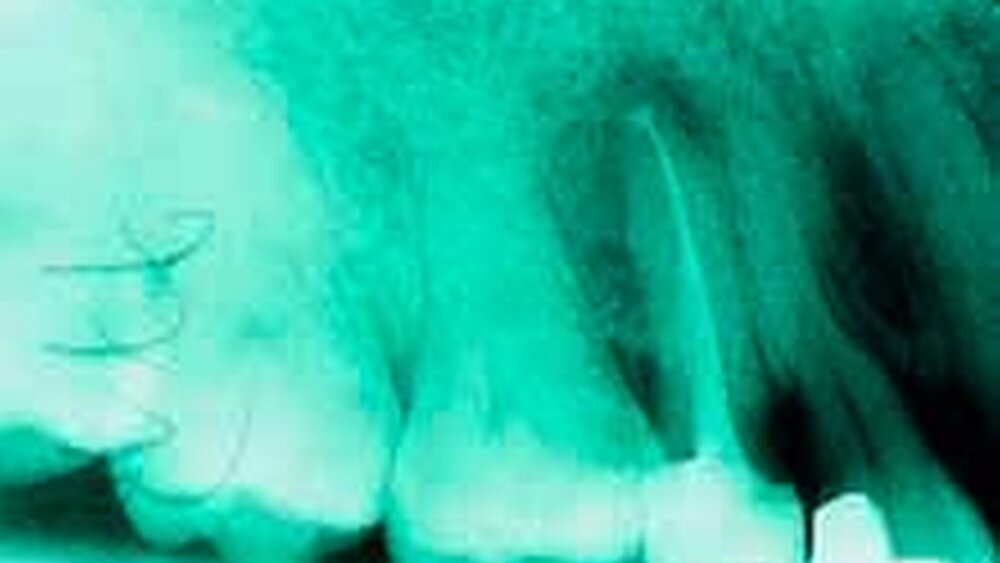

Im zweiten Theorieblock berichtete Professor Baumann über Neuigkeiten im Bereich der Längenmessung. Es wurden sowohl die röntgenologische und endometrische Längenmessung als auch die so genannte Paperpointmethode angesprochen. Für die in der eigenen Praxis tätigen Zahnärzte waren Abrechnungstipps sehr interessant und motivierend, die Endodontologie im Seitenzahnbereich nicht aus der Praxis verschwinden zu lassen.